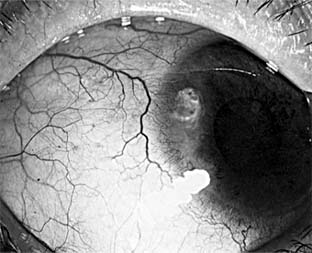

Pseudomonas corneal ulcer begins as a gray or yellow infiltrate at the site of a break in the corneal epithelium (Figure 6-2). Severe pain usually accompanies it. The lesion tends to spread rapidly in all directions because of the proteolytic enzymes produced by the organisms. Although superficial at first, the ulcer may affect the entire cornea. There is often a large hypopyon that tends to increase in size as the ulcer progresses. The infiltrate and exudate may have a bluish-green color. This is due to a pigment produced by the organism and is pathognomonic of P aeruginosa infection.

Figure 6-2

Figure 6-2: Pseudomonsa ulcer related to 24-hour contact lens wear.